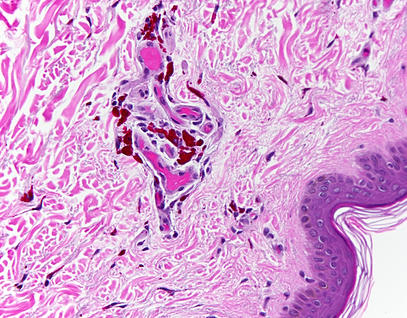

The Mütter Museum is best known for the Hyrtl Skull Collection and other anatomical specimens including a wax model of a woman with a horn growing out of her forehead along with several wax molds of untreated conditions of the head; the tallest skeleton currently on display in North America; a nine-foot-long human colon that contained over 40 pounds of fecal matter when removed from the remains of a man who appeared in a sideshow act called the Human Balloon; and the body of the Soap Lady, whose corpse turned itself into a soapy substance called adipocere better known as grave wax. Many wax models from the early 19th century are on display as are numerous preserved organs and body parts.

- A collection of teratological specimens (preserved human fetal specimens) all of which were donated to science

- A malignant tumor removed from President Grover Cleveland's hard palate

- The conjoined liver from the famous Siamese twins Chang and Eng Bunker

- A piece of tissue removed from the thorax of Abraham Lincoln's assassin, John Wilkes Booth

- A section of the brain of Charles J. Guiteau who assassinated U.S. President James A. Garfield